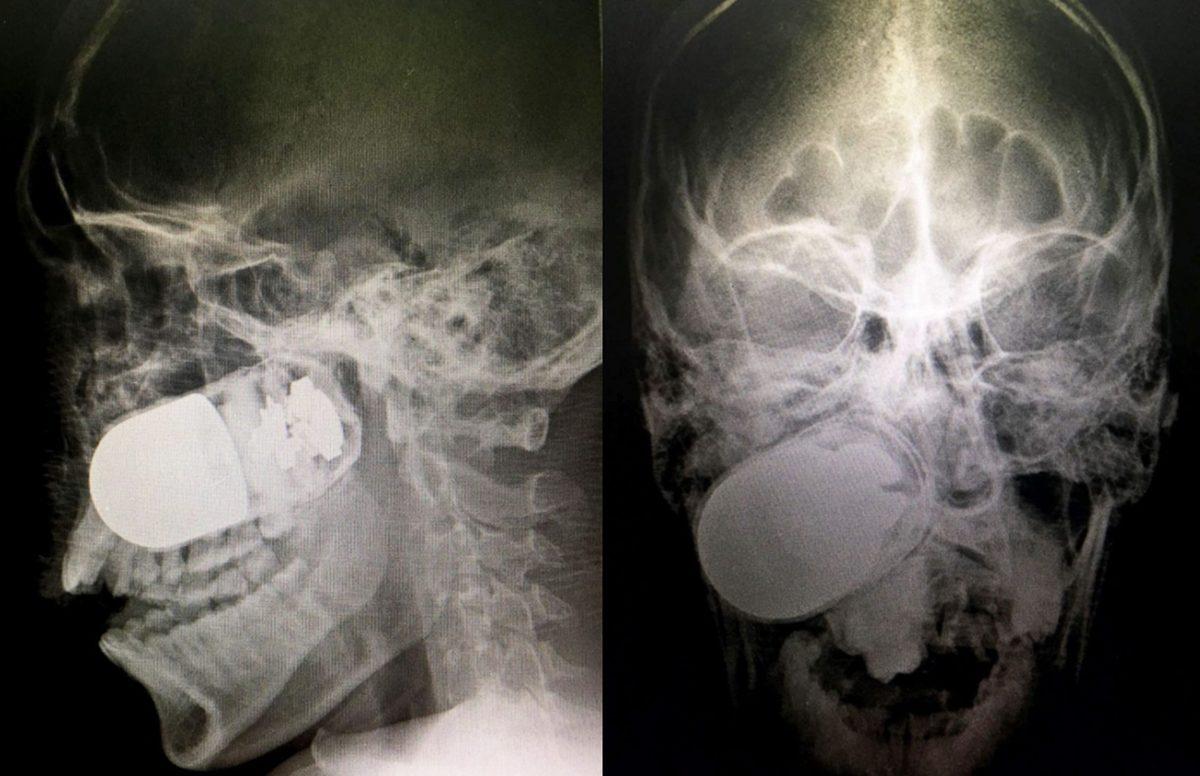

- "Mısır gevreği yerken" çenesi çıkan biri.

- El bombası yutan bir terörist. Bilmediği şeyse pimini çekmeden yuttuğu için asla patlatılamayacağıydı.

- Bir Kolombiyalı askerin yüzüne giren bomba.

Ameliyathanede patlamasından korktukları için hastanenin otoparkında sağlık personeli tarafından başarıyla çıkarılmış.

- Pakistan'da yaşayan bu kadının kafasına 5 cm'lik çivi girmesi her ne kadar ilginç olsa da bunun yaşanma sebebi çok daha ilginç.

3 kızı olan bu kadın, kocasının erkek çocuk istemesi üzerine hocaya gidiyor ve bu hoca, bebeğin erkek olması için kadının kafasına çivi çakıyor!